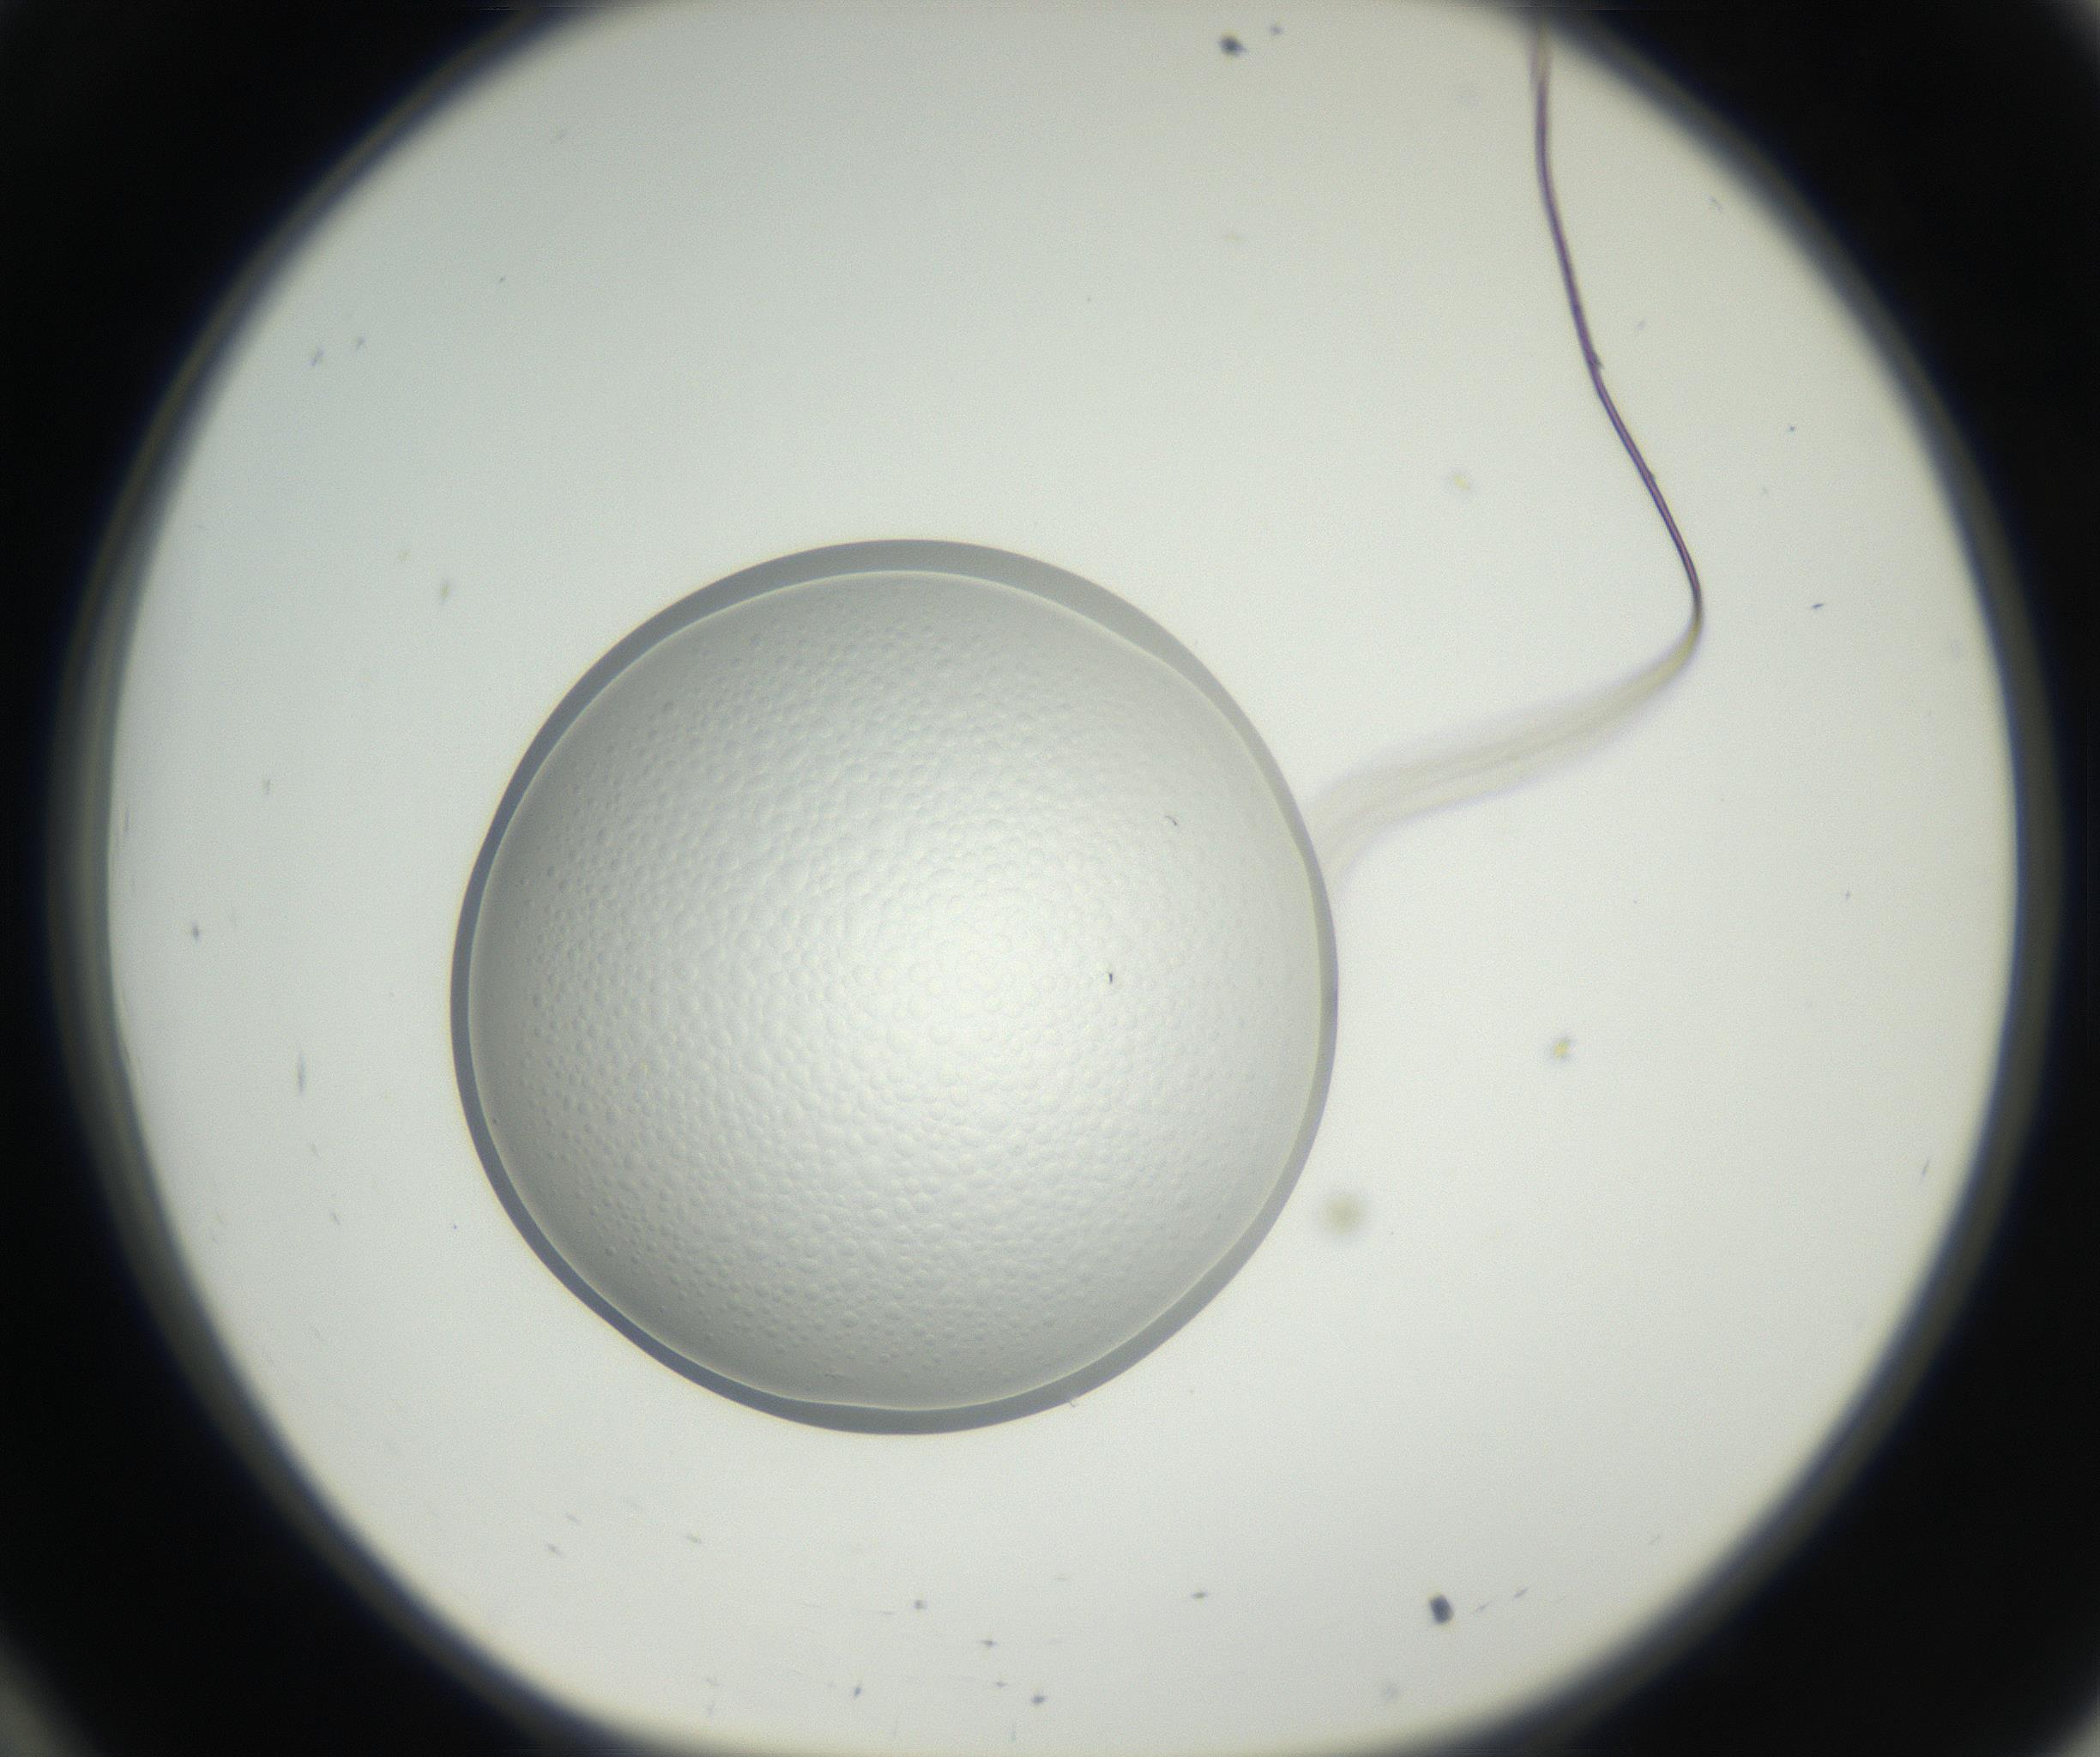

RI01_03_000_0212_Proj1_Clon1_MC_0000MC011158_004_160807_10_03_01_00_99_002_001_RAI.jpg